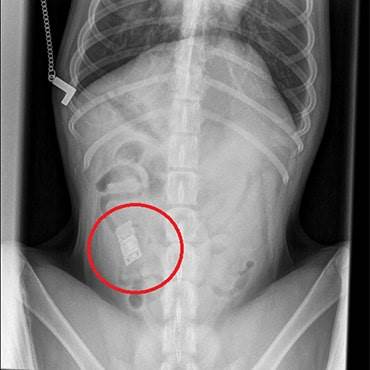

Rocco was admitted immediately and our vets were stunned when x-rays revealed a rectangular shaped object in his gut. After rushing him into surgery to remove the potentially fatal object, they retrieved a video game cartridge lodged in his small intestine!

Left untreated, the cartridge could have caused a fatal blockage. Our experienced surgeon was able to carry out the successful operation that same day and after an overnight stay to keep a close eye on his recovery Rocco was discharged the following day for rest and recovery.